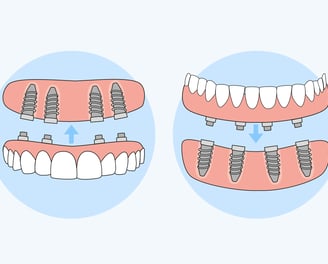

Son dentaduras que se apoyan sobre implantes dentales para mejorar su estabilidad y retención. Ofrecen una solución más segura y cómoda en comparación con las dentaduras tradicionales

Sobredentaduras

Combinan características de las prótesis fijas y removibles, generalmente ancladas a implantes dentales para mayor estabilidad. Son una solución intermedia que ofrece flexibilidad y soporte.

Colocación de prótesis híbridas